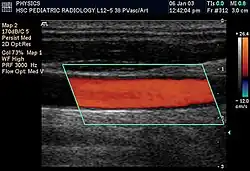

Doppler ultrasonography is used to study blood flow and muscle motion. The different detected speeds are represented in color for ease of interpretation, for example leaky heart valves: the leak shows up as a flash of unique color. Colors may alternatively be used to represent the amplitudes of the received echoes.

Doppler ultrasonography

Doppler ultrasonography employs the Doppler effect to assess whether structures (usually blood)[59][62] are moving towards or away from the probe, and their relative velocity. By calculating the frequency shift of a particular sample volume, flow in an artery or a jet of blood flow over a heart valve, its speed and direction can be determined and visualized, as an example. Color Doppler is the measurement of velocity by color scale. Color Doppler images are generally combined with gray scale (B-mode) images to display duplex ultrasonography images.[63] Uses include: